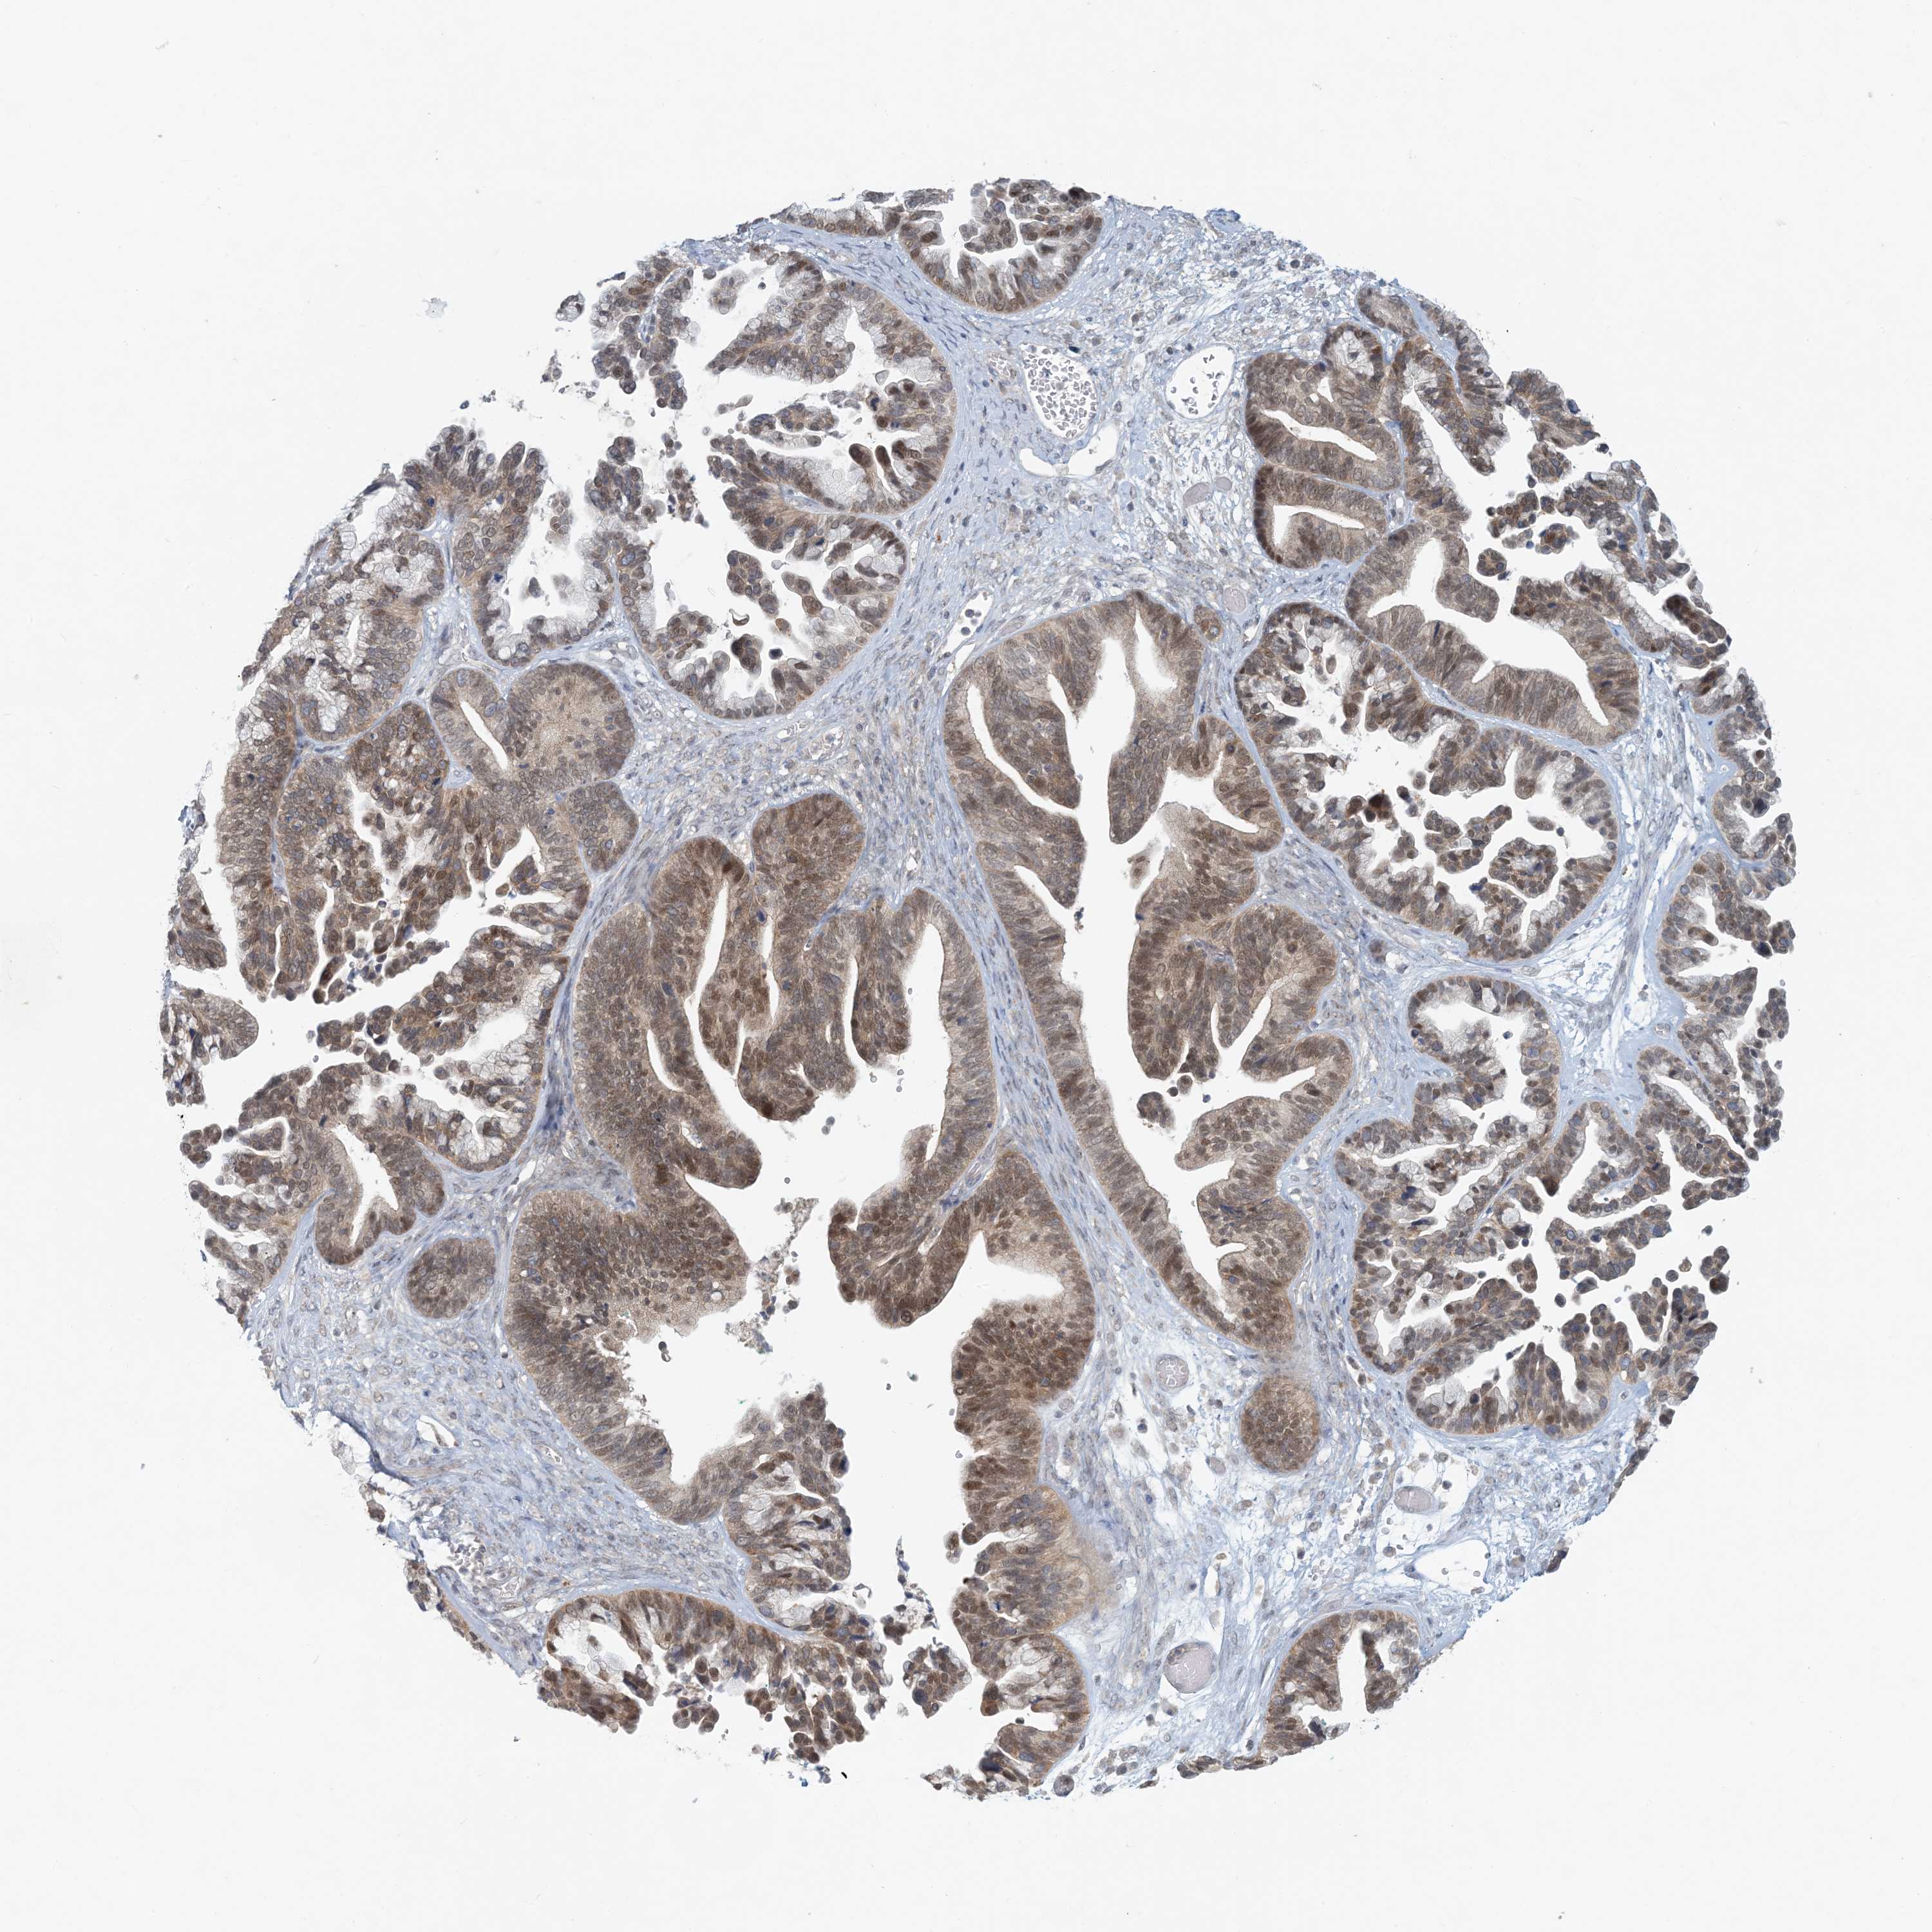

OVARIAN CANCER - Protein expressioni

A mouse-over function shows sample information and annotation data. Click on an image to view it in a full screen mode. Samples can be filtered based on level of antibody staining by selecting one or several of the following categories: high, medium, low and not detected. The assay and annotation is described here.

Note that samples used for immunohistochemistry by the Human Protein Atlas do not correspond to samples in the TCGA dataset.

Antibody stainingi

Antibody staining in the annotated cell types in the current human tissue is reported as not detected, low, medium, or high, based on conventional immunohistochemistry profiling in selected tissues. This score is based on the combination of the staining intensity and fraction of stained cells.

Each image is clickable and will lead to virtual microscopy that enables deeper exploration of all samples and also displays staining intensity scores, fraction scores and subcellular localization as well as patient and tissue information for each sample.

Antibody HPA034785

Antibody HPA034786

Staining

High

Medium

Low

Not detected

Intensity

Strong

Moderate

Weak

Negative

Quantity

>75%

75%-25%

<25%

None

Location

Nuclear

Cytoplasmic/membranous

Cytoplasmic/membranous,nuclear

Cystadenocarcinoma, serous, NOS